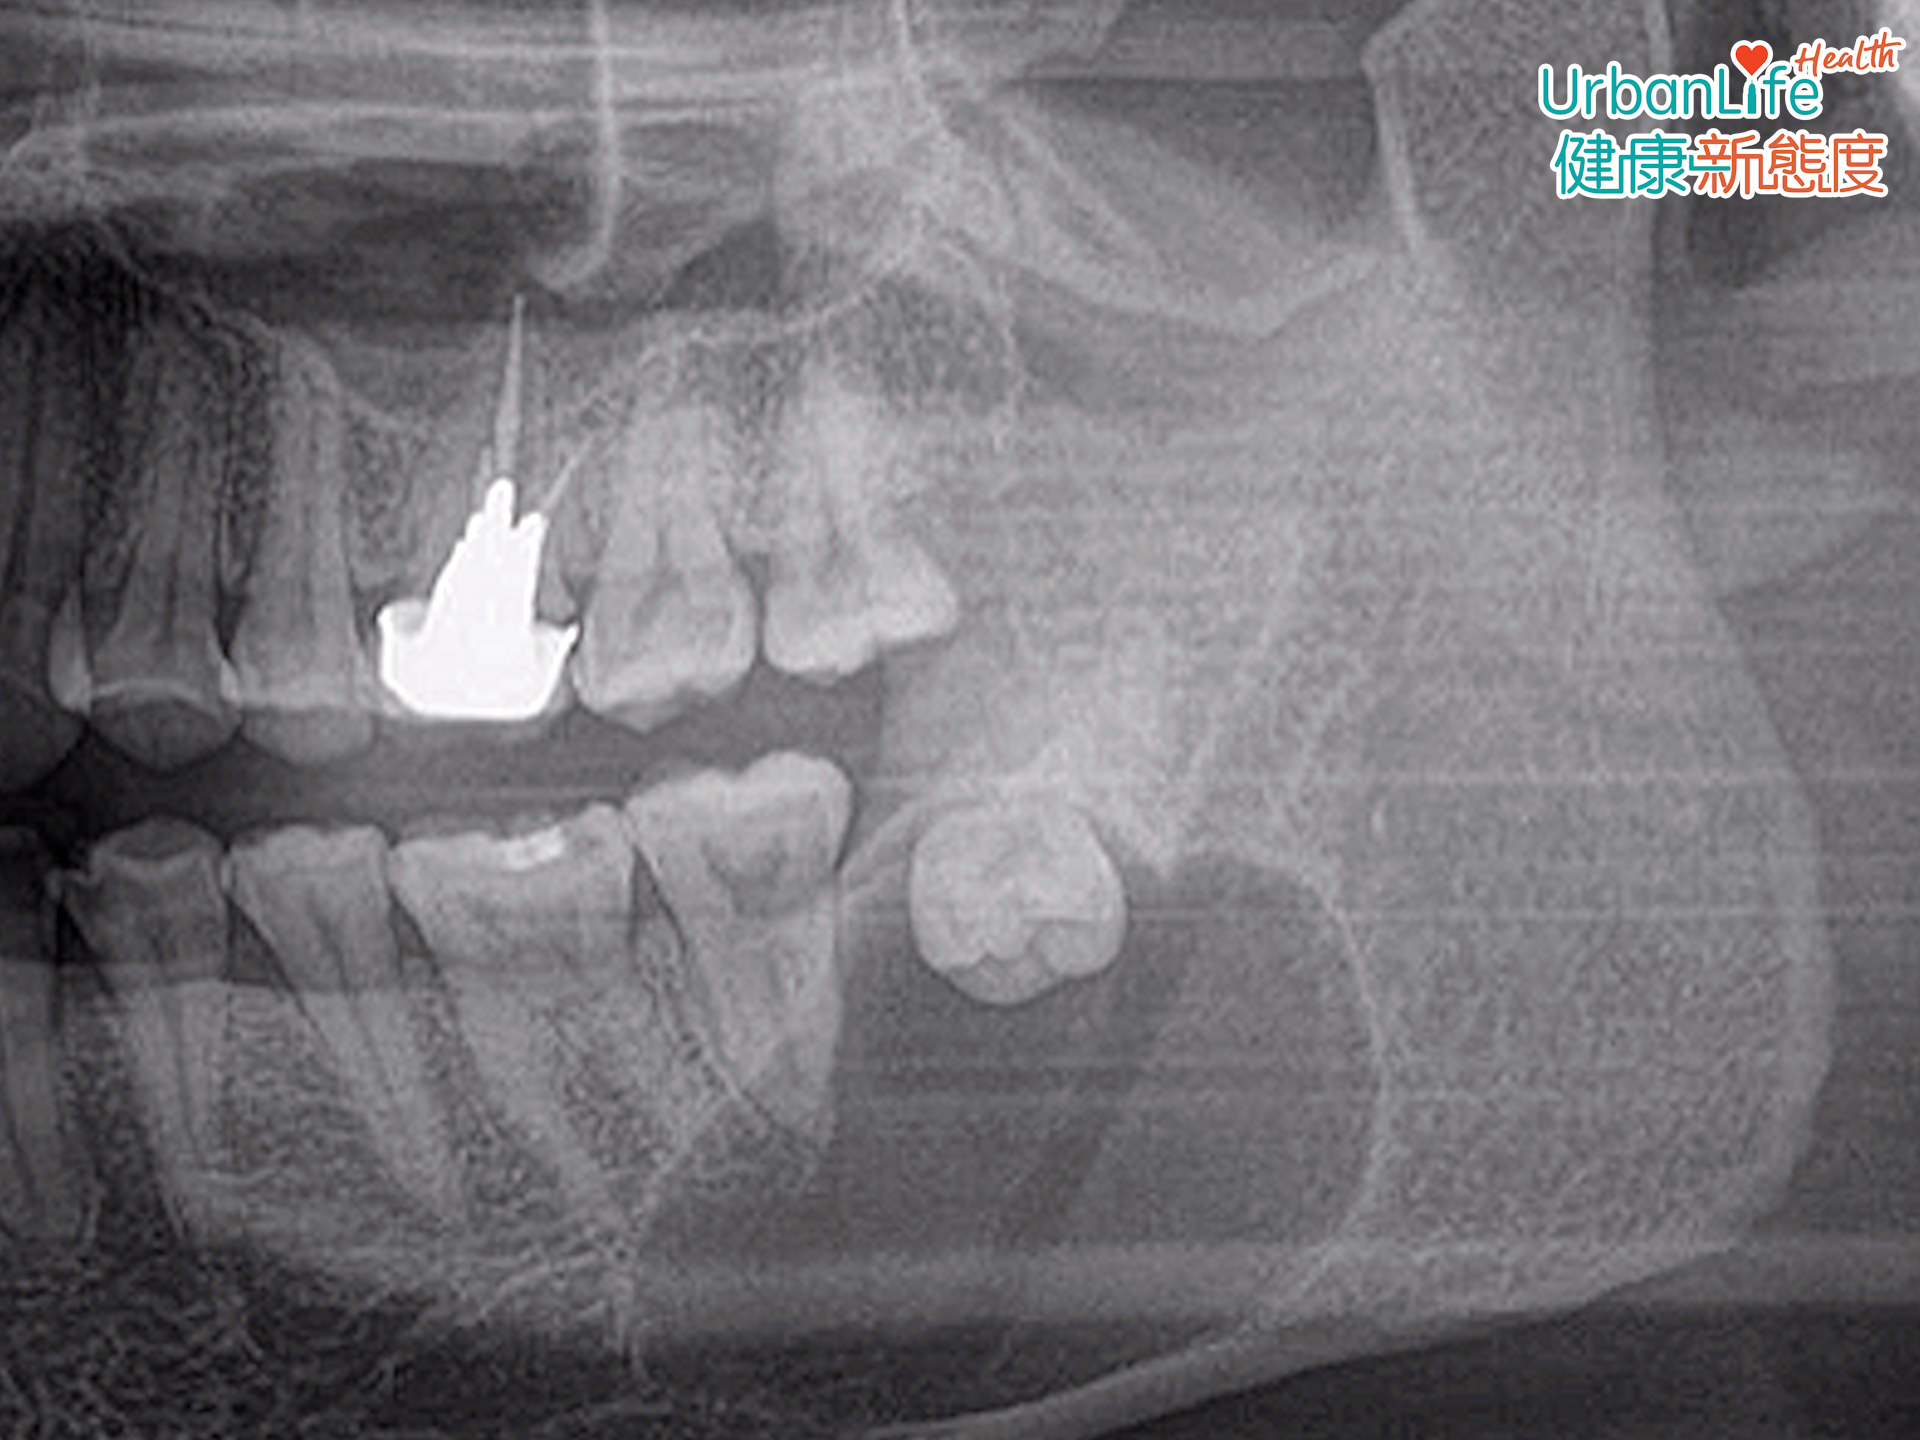

10多歲生智慧齒無按醫囑拔除 20年後水瘤病變要開刀

他分享了一個臨床個案,指有一名30多歲患者,求醫時已發現其有一個很大的水瘤包圍著智慧齒。詢問後發現,原來該名患者早於10多歲時,便知道自己有一隻智慧齒,而當時牙醫已叫他拔除,可惜他多年來也沒有正視處理,期間亦沒有出現疼痛不適。

最終需要做一個全身麻醉手術,將水瘤拿出,而因水瘤下方也有一條神經線,醫生要很小心將神經線與水瘤分離,才成功避免神經線受損。